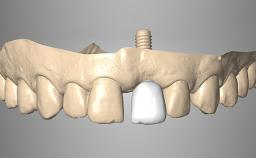

Rehabilitating an Edentulous Maxilla with a Fixed Dental Prosthesis Using a DSD-Guided Approach

A 60-year-old man was referred to the Center of Excellence for Prosthodontics and Implant Dentistry (CEPI) of the School of Dentistry of the University of São Paulo, Brazil for implant therapy. Anamnesis, clinical examination, and radiographs revealed esthetic and functional problems, the absence or structural compromise of various teeth (16–11, 21, 22, 24, 25, 37, 45, and 48), periodontal and endodontic problems (17 and 27), implant fracture (46), and occlusal disorders . The patient reported that he was undergoing treatment for cardiovascular diseases.

# of Implants 4

Prosthesis Type FDP

Loading Protocol Immediate